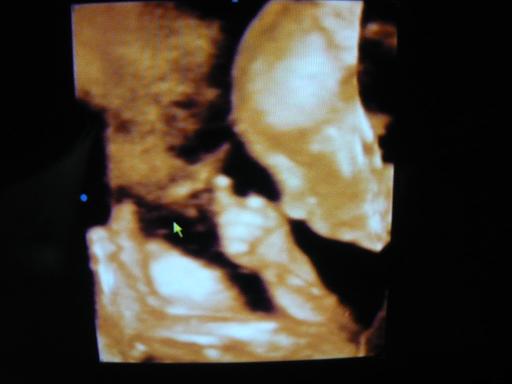

Akkor majd Te is hozz az ikrekről 4D-s képet!